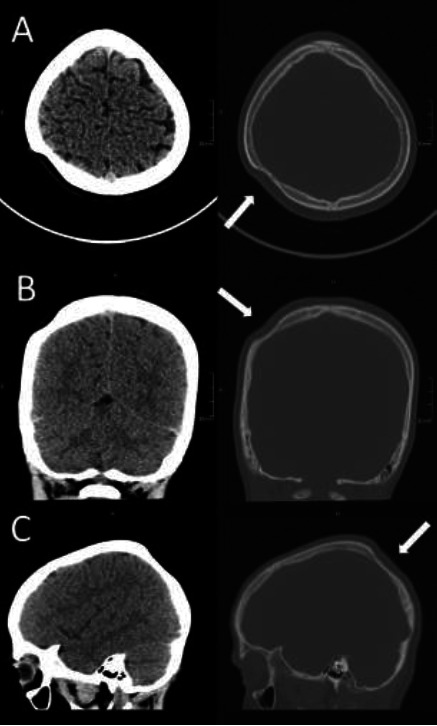

Idiopathic focal unilateral skull thinning is a rare finding. An explanation, such as trauma or disease, can often be found. However, in some cases, no explanation is forthcoming, and thus, we must look further into their history for a possible cause. The case of a nine-year-old boy with a crescent-shaped unilateral parietal bone thinning and a history of ventouse-assisted birth is presented. The lesion matches a ventouse's typical location, shape, and size. Thus, with the support of one other reported similar case, we hypothesise this may be the origin. We present the case of a crescent-shaped lesion matching the imprint of a ventouse in a child with a concordant history. This finding is put in the context of similar reports in the literature, and we believe that this report provides further evidence of this obscure phenomenon.